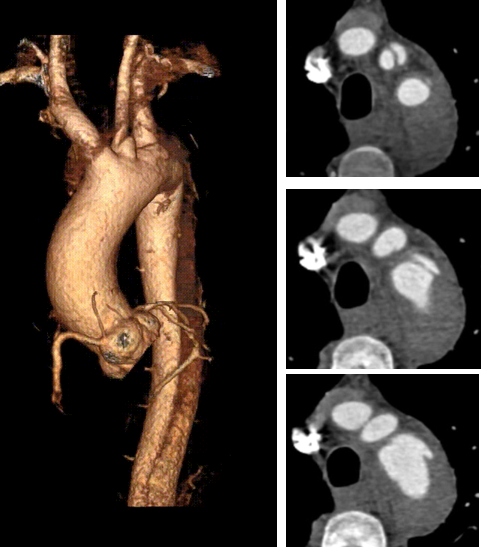

★ 病例2:模块内嵌分支胸主动脉覆膜支架系统

术前

术后